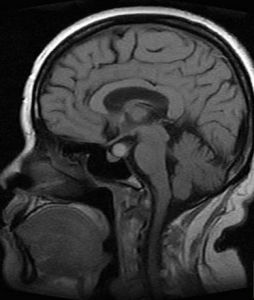

9、磁共振成像(MRI)是近年套用於臨床的新檢查方法。在腦炎期病灶呈邊緣不清的高信號改變,中心壞死區為低信號改變,T2(橫弛豫時間)延長,周邊腦水腫也呈高信號變化,灰白質對比度消失,T1(縱弛豫時間)和T2也延長。腦炎晚期的病灶中央低信號區擴大,IR(反向復原)成像示中央區仍為低強度。包膜形成期的中央區低信號,T1延長,但在長TR(重複時間)成象時原低信號變成較腦脊液高的高信號。包膜則為邊界清楚的高信號環。鄰近腦灰白質對比度恢復正常,但T1,T2仍輕度延長。因此MRI顯示早期腦壞死和水腫比CT敏感,區分膿液與水腫能力比CT強,但在確定包膜形成,區分炎症與水腫不及CT敏感。

5、電子計算機斷層腦掃描(CT)及磁共振成像檢查(MRI):自從CT及MRI用於臨床,對顱內疾患,尤其占位病變的診斷有了重大突破。CT可顯示腦膿腫周圍高密度環形帶和中心部的低密度改變。MRI對膿腫部位、大小、形態顯示的圖像信號更準確。由於MRI不受骨偽影的影響,對幕下病變檢查的準確率優於CT。CT和MRI能精確地顯示多發性和多房性腦膿腫及膿腫周圍組織情況。